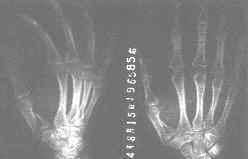

本型骨折的X線特點是第一掌骨近端基底部凹形關節面的一半骨折,一半脫位。骨折線從凹形關節面的中心斜行向掌側約1cm處,骨折塊留在掌、尺側多無移位,而第一掌骨基底部的其餘部分受外展拇長肌的牽拉和拇屈肌的收縮向背、外側半脫位,第一掌骨向掌側屈曲